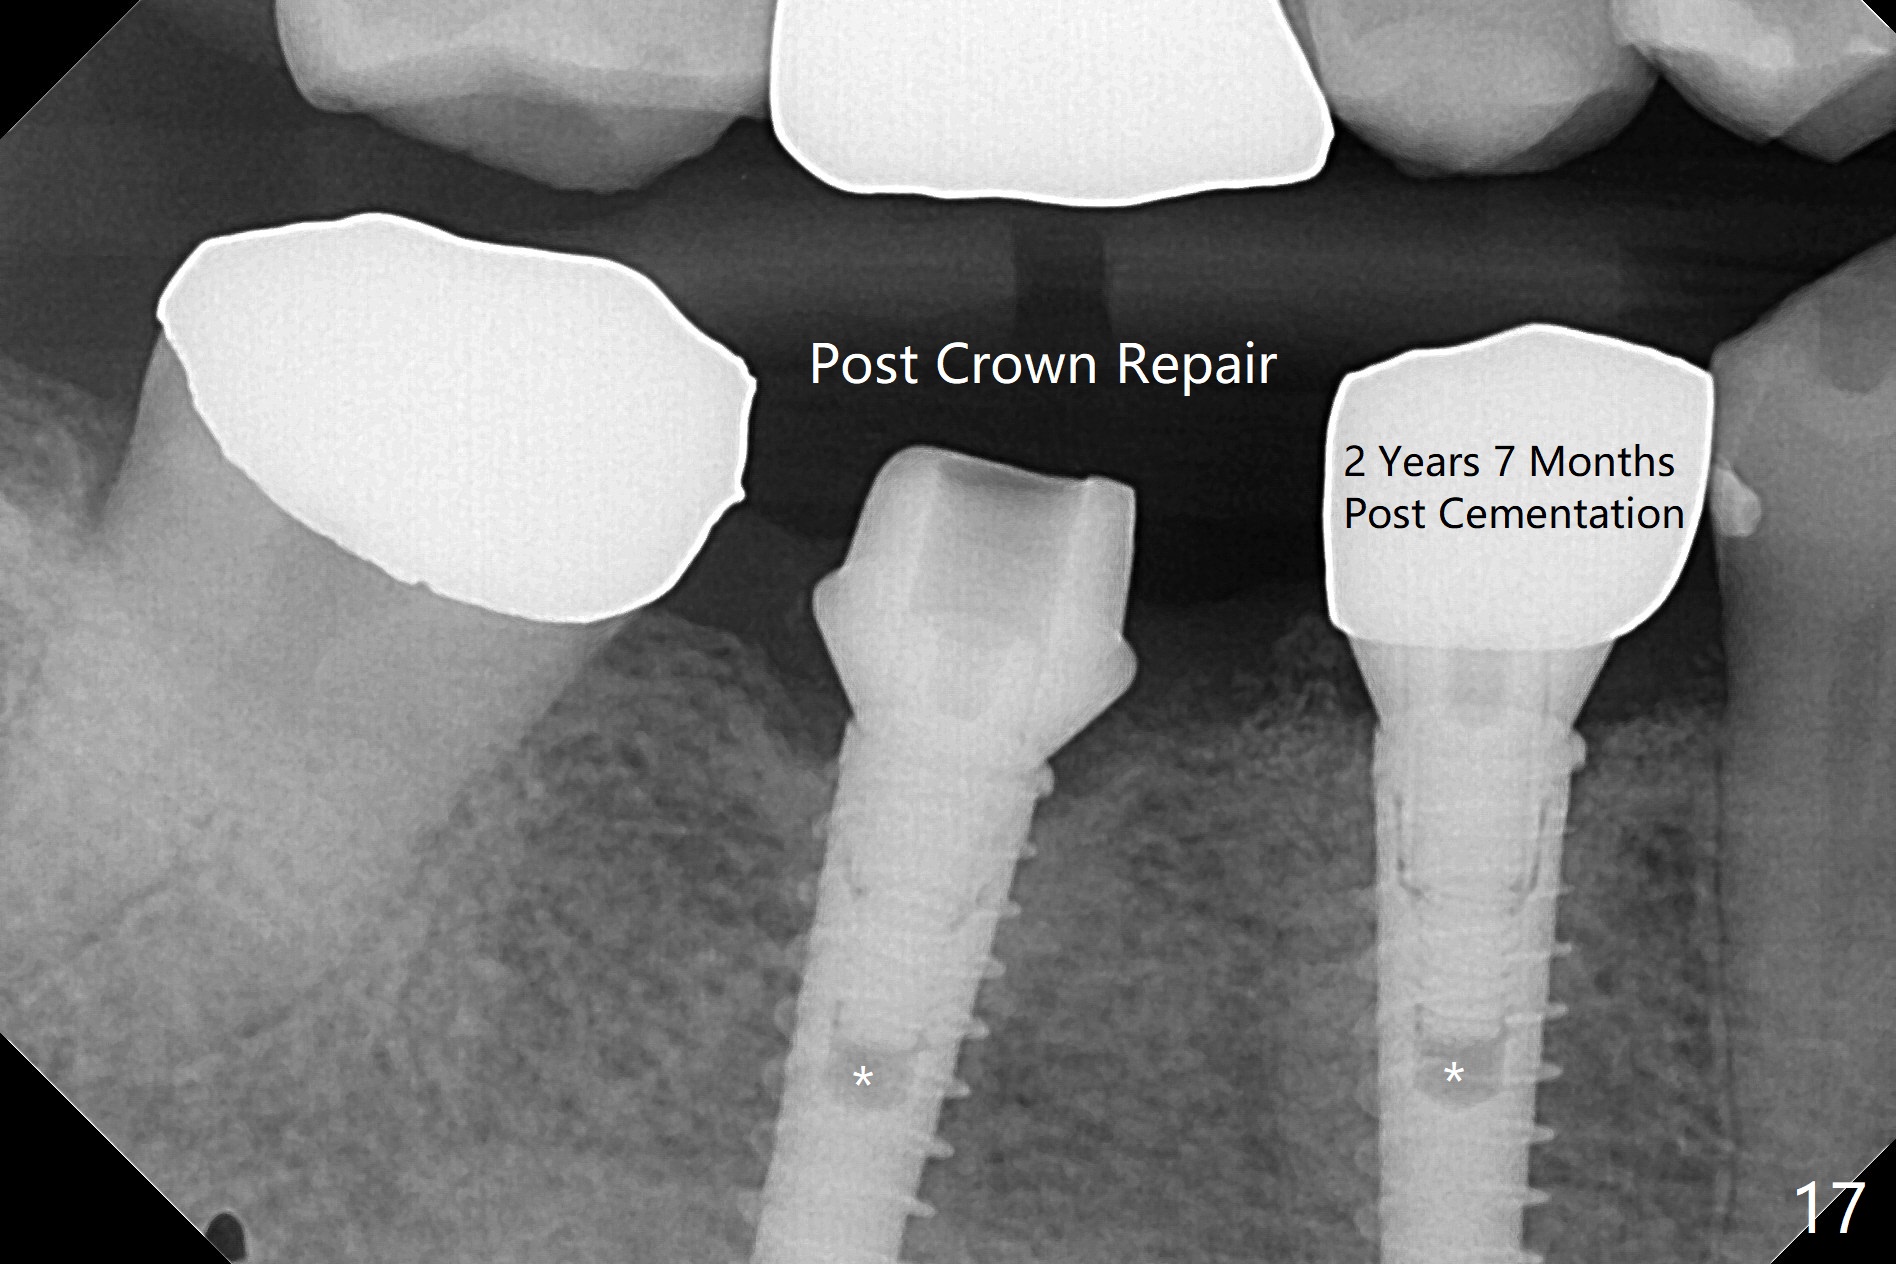

After incision, the ridge at #29 and 30 is found ~ 5 mm wide buccolingually. To place a 4x11 mm IBS implant at #30, the ridge is expanded using BEB technique (bone expansion and bending, Fig.1). It appears that the initial osteotomy at #29 is mesial (Fig.1 yellow dashed line: the distal surface of the root of the tooth #28). After moving the osteotomy distal, the final implant position at #29 (4x11 mm) is within normal limit (Fig.2). The bone at #29 seems to be not so dense that bending (using 1.6 mm drill) is not necessary (using Magic Split and Magic Expanders 3 and 3.8 mm). Later the implant at #30 (4x11 mm) is placed deeper (Fig.3). After placing bone graft around the implants/abutments and suturing, the ridge looks wider with apparent formation of the gingival bands around the abutments (Fig.4 *). Three months and a half postop, bone loss is minimal (Fig.5) and gingival bands forms around the abutments (Fig.6). Fig.7 is taken 1 month post cementation (panoramic X-ray). The patient chews normally 1 year (Fig.8) and nearly 2 years (Fig.9,10) post cementation. The crown at #31 needs recementation 2 years 7 months post #30 cementation; the incomplete seating of the abutment was noted for the first time (Fig.11). Five months later the patient is going to be retired and wants to travel abroad. After approval, the access hole was reopened; articulating paper shows under occlusion of the crown (Fig.12). Since the gap between the abutment and the implant is large, the abutment/crown complex seems to be necessary to be turned (Fig.13 curved arrow). The proximal surfaces of the crown need to be trimmed (straight lines). After turning, the crown sits down with screw tightening; the patient feels pain from the gingival cuff (Fig.14). After turning, the abutment appears to be completely seated (Fig.15). In fact the mesial and distal surfaces of the crown should have clearance from the neighboring teeth (Fig.14) so that pick-up impression is able to hold the crown/abutment complex securely (Fig.16: *). The crown is separated from the abutment after crown repair. They are seated together (loose connection) using the crown as a guide to seat the abutment. BW is taken without the crown. It appears that the abutment remains seated completely (Fig.17). The apical space is equal between #29 and 30 (Fig.17, as compared to Fig.5).